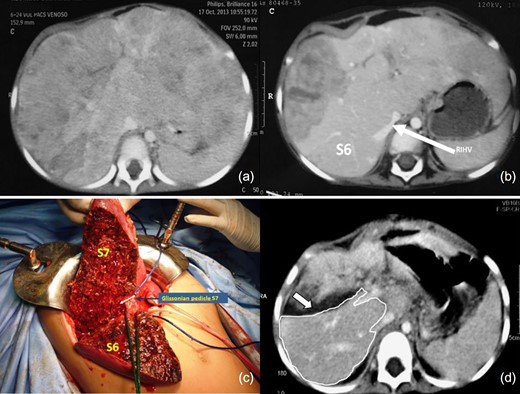

Tumor staging revealed a PRETEXT IV hepatoblastoma (Fig. 1a) with Alpha-fetoprotein (AFP) levels of 1 059,240 ng/ml. After 15 days in the ICU, when the patient’s condition had improved, we initiated NACT (3 courses of Doxorubicin and Carboplatin). At its completion, the AFP levels had decreased to 1 573 ng/ml and a follow-up CT scan showed tumor involvement of segments 1-7 except for s6 (POST-TEXT IV). The latter segment was vascularized through the IRHV but it was deemed insufficient (FLR 21.34%) (Fig. 1b). The absence of a liver donor within reasonable time prompted a multidisciplinary committee meeting that approved an ALPPS procedure after securing informed consent from the parents.

(a) Tumor staging CT (PRETEXT IV), shows all liver sections being invaded by tumor (b) The CT scan post NACT indicates partial tumor response, with persistence of tumor compromising the four sections (POST-TEXT IV). The IRHV is identified (white arrow). No tumor is visible in s6 (c) First stage of ALPPS, the posterior pedicle and its branches were tagged and s7 pedicle clipped (d) FLR on PO15 is outlined in white. The white arrow shows the transection plane.

The patient underwent the first stage on April 9, 2014. An initial exploratory laparotomy confirmed absence of extrahepatic disease, and we also found firm adhesions as result of the hemoperitoneum caused by the biopsy that required the laparotomy with liver packing. All segments were found to have macroscopic disease except for segment 6 (Fig. 1c). A careful hilar and pedicle dissection was executed, with particular attention being paid to the posterior division and inferior hepatic vein. The left portal vein was ligated, and the other elements of the liver pedicle (including the anterior branch of the right portal vein) were tagged for the second stage. Transection was carried out with a Cavitron Ultrasonic Surgical Aspirator (CUSA) with the intention of identifying and preserving the segment six pedicle. The s7 pedicle was then clipped with the expectation of segment necrosis, which was confirmed in a postoperative CT scan. An estimated blood loss of 1 600cc prompted a transfusion of 750cc of red blood cells. Total operative time was 6 hours. The patient returned to the ICU and had an uneventful postoperative course after the first stage. Liver volumetry on POD 15 showed an FLR (segment 6) of 120cc (32.57%) (Fig. 1d).